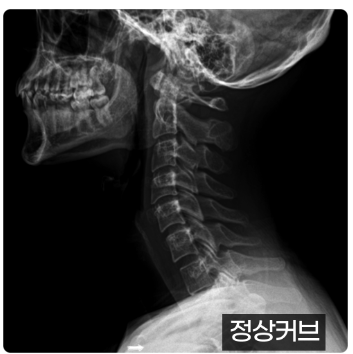

왜 일자목이 되면 온몸이 아플까요?

일자목이 되면 머리 무게를 지탱하는 근육과 인대에 부담이 크게 증가합니다.

정상적인 C자 곡선이 있을 때보다 2~3배 더 힘이 들어가 주변 근육 문제도 쉽게 생기죠.